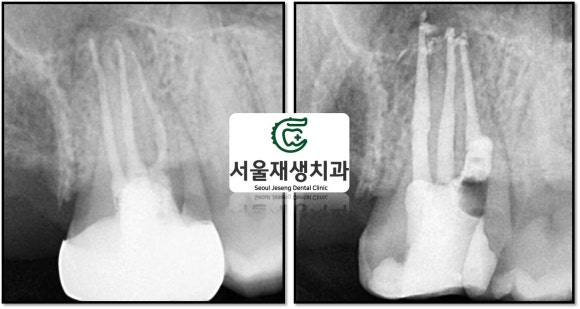

치료 전, 그리고 재신경치료가 끝난 직후에 촬영한 사진입니다.

이전 치료에서 미흡했던 부분들을

다시 한 번 꼼꼼히 청소 후 밀봉하였습니다.

재신경치료의 마지막 단계, 크라운 장착

환자분 입 안에서 오래오래 튼튼하게 일하라고, 보이는 쪽은 도자기, 안 보이는 쪽은 금속으로 튼튼하게 만들어드렸습니다.